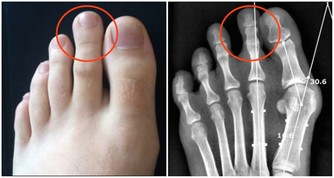

5、下肢浮腫,顏面胖腫,腹圍增加,出現腹水者;